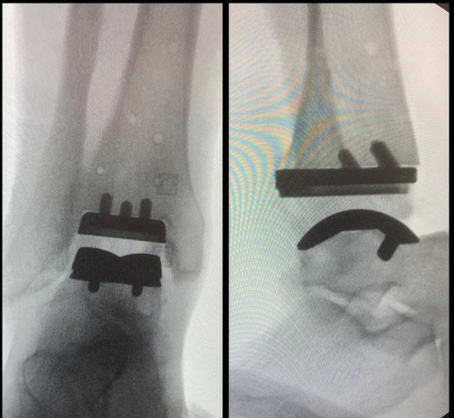

ARTROPLASTIA DE TORNOZELO!

Você sabia que existem próteses para o tornozelo? E que tem melhorado e muito a qualidade de vida de pacientes com artrose ( desgaste)...